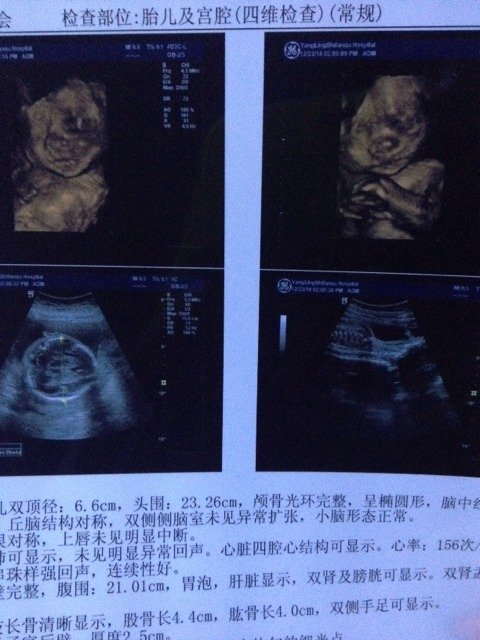

今天做四维回来了,谁能帮我看看男该还是女孩 今天做四维回来了,谁能帮我看看男该还是女孩 点击展开 Zmeimei 2014-12-23 17:41 为您推荐: 其他回答 可能吗?哄你干嘛对我没什么好处,我是算出来的 鑫茹妈妈 2014-12-23 22:42 看不出来!! 我不记得我爱过 2014-12-23 21:21 看图啊,看人 你是我的小苹果。 2014-12-23 20:42 基本上是男宝。 你是我的小苹果。 2014-12-23 20:20 不太会看。 春天绿茶 2014-12-23 19:28 加载更多 相关问题 今天的四维!懂的人看的出是男还是女孩不?谢谢啦 今天做了四维医生说80%是女孩,像是小x,小x是什么意思啊,是不是就肯定是女孩了 32周两天照的四维结果,大家帮我看看都正常不,顺便看看是男孩还是女孩,谢谢!胎位loa,颅骨近圆形